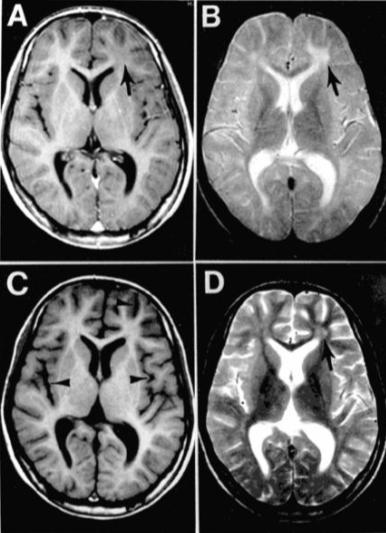

写真:sciencebasedmedicine.org

病名がどうしても気になるという人のために、日本ではほとんど見られない、非常に珍しい病気をいくつかピックアップしてみました。1つ目は亜急性硬化性全脳炎という病気で、英語での病名の頭文字からSSPEと呼ばれることもあります。麻疹ウイルスによって非常にゆっくりと進行する脳炎の一種で、感染してから5年から10年ほどの潜伏期間を経て発病します。発病後も数年をかけて神経症状が進行し、完治させる治療法もなく予後も悪い難病です。